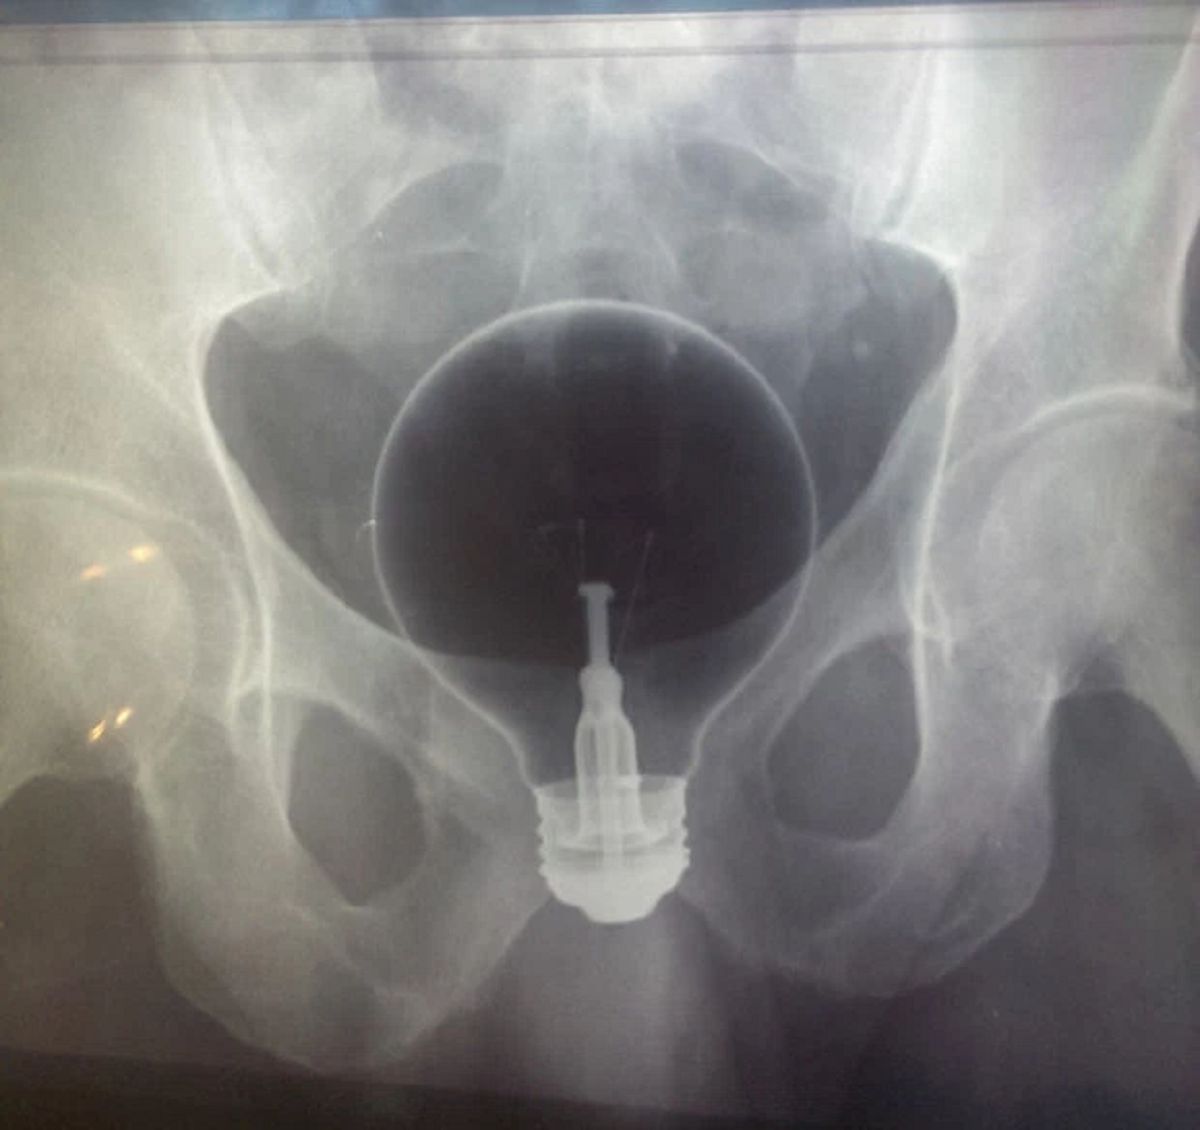

/ 8Żarówka

Ponoć wpadła tam przypadkowo. Ale okoliczności pacjent nie chciał zdradzić...